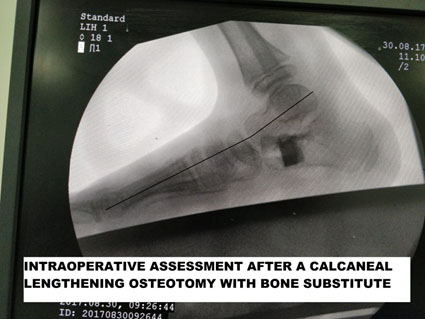

ORTHOPEDIC SURGERY OF THE FOOT

Equinoplanovalgus deformity

Equnioplanovalgus is a reasonably common deformity in cerebral palsy. The child walks with pronation or more on the inner border of the foot with minimal contact on the outer edge leading to a bad flat foot and painful gait. The foot works like a tripod, and any malalignment leads to problems in gait. Firstly, orthotics are prescribed in mild deformity. Severe deformity necessitates calcaneal lengthening as well as soft tissue surgery to rebalance the muscular forces.